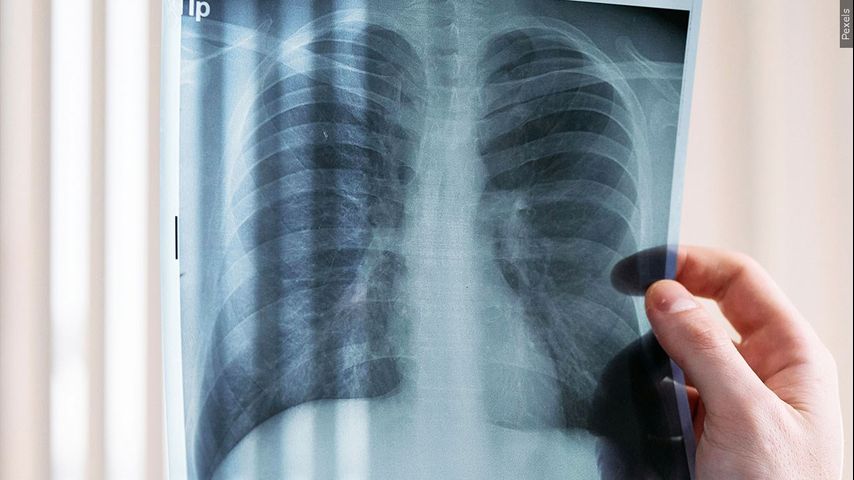

NEW ORLEANS - As part of National Cancer Prevention Month, the American Lung Association is offering free lung cancer screenings to residents of six parishes who face higher risk.

Residents in Acadia, Avoyelles, Evangeline, St. Landry, Terrebonne and Tangipahoa parishes are eligible for the screenings. They must also be between 50 and 80 years old, have a 20 pack-year history of smoking (one pack a day for 20 years or two packs a day for 10 years) and they must currently smoke or have quit smoking within the last 15 years.